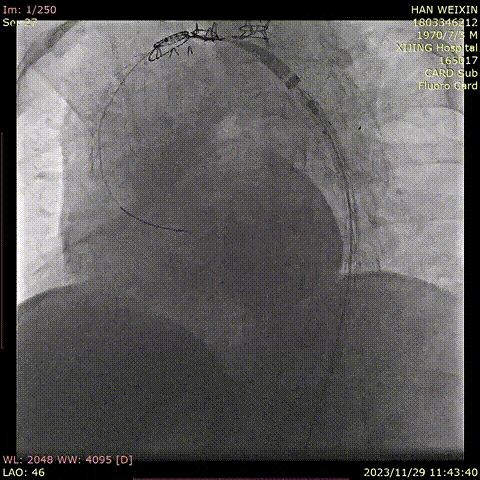

韩某,男,53岁,“查体发现主动脉弓部溃疡15天”入院,主动脉CTA提示:主动脉溃疡(弓部);2. 主动脉壁内血肿。患者高血压病史8年,最高210/130mmHg,无规律服药。

术前 CTA

术前造影

手术用时115分钟